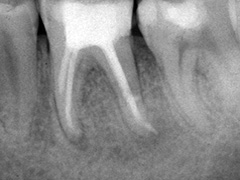

Aufbissempfindlichkeit an 33 veranlasste uns erstmalig in dieser Kieferregion zu röntgen. Mit grossen Augen sahen wir dann an, was uns auch ansah. Einen Knochendefekt dieser Grössenordnung mit seiner schaurigen Aura sieht man zum Glück nicht jeden Tag. Doch, obgleich das Alien dereinst Zahn 34 entsprang, war eine Behandlung nur am Zahn davor durchsetzbar. Dessen Wurzelfüllung erfolgte regulär nach 14 Tagen, neue Terminangebote aber wurden, weil angeblich nicht mehr nötig, verschmäht.

3 Aufnahmen sind von 2001, die vierte vom Nov. 2006